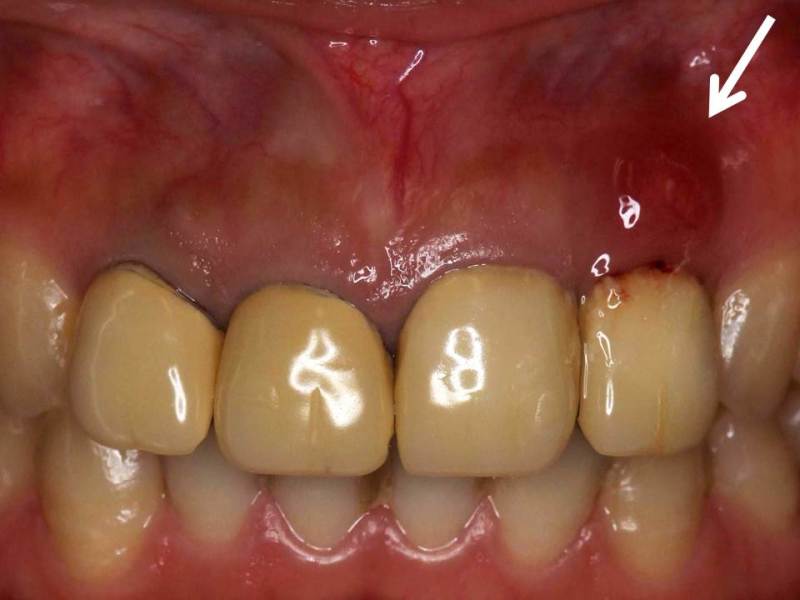

初診時。水平性歯根破折により、歯茎の腫れが見られる。保険のクラウンが装着されており、色の変色とブラックマージン(歯と歯茎の間の黒ずみ)を生じている。著しく審美性が悪い。

比較的浅い部分での水平性歯根破折であったため、矯正的挺出を試みる。

まず、破折した部分を取り除き、根管治療を完全に行ったあとに仮歯を装着する。仮歯の裏側から矯正装置を装着し(→)ゴムを使用して骨の中から歯根を徐々に引っ張り出す。